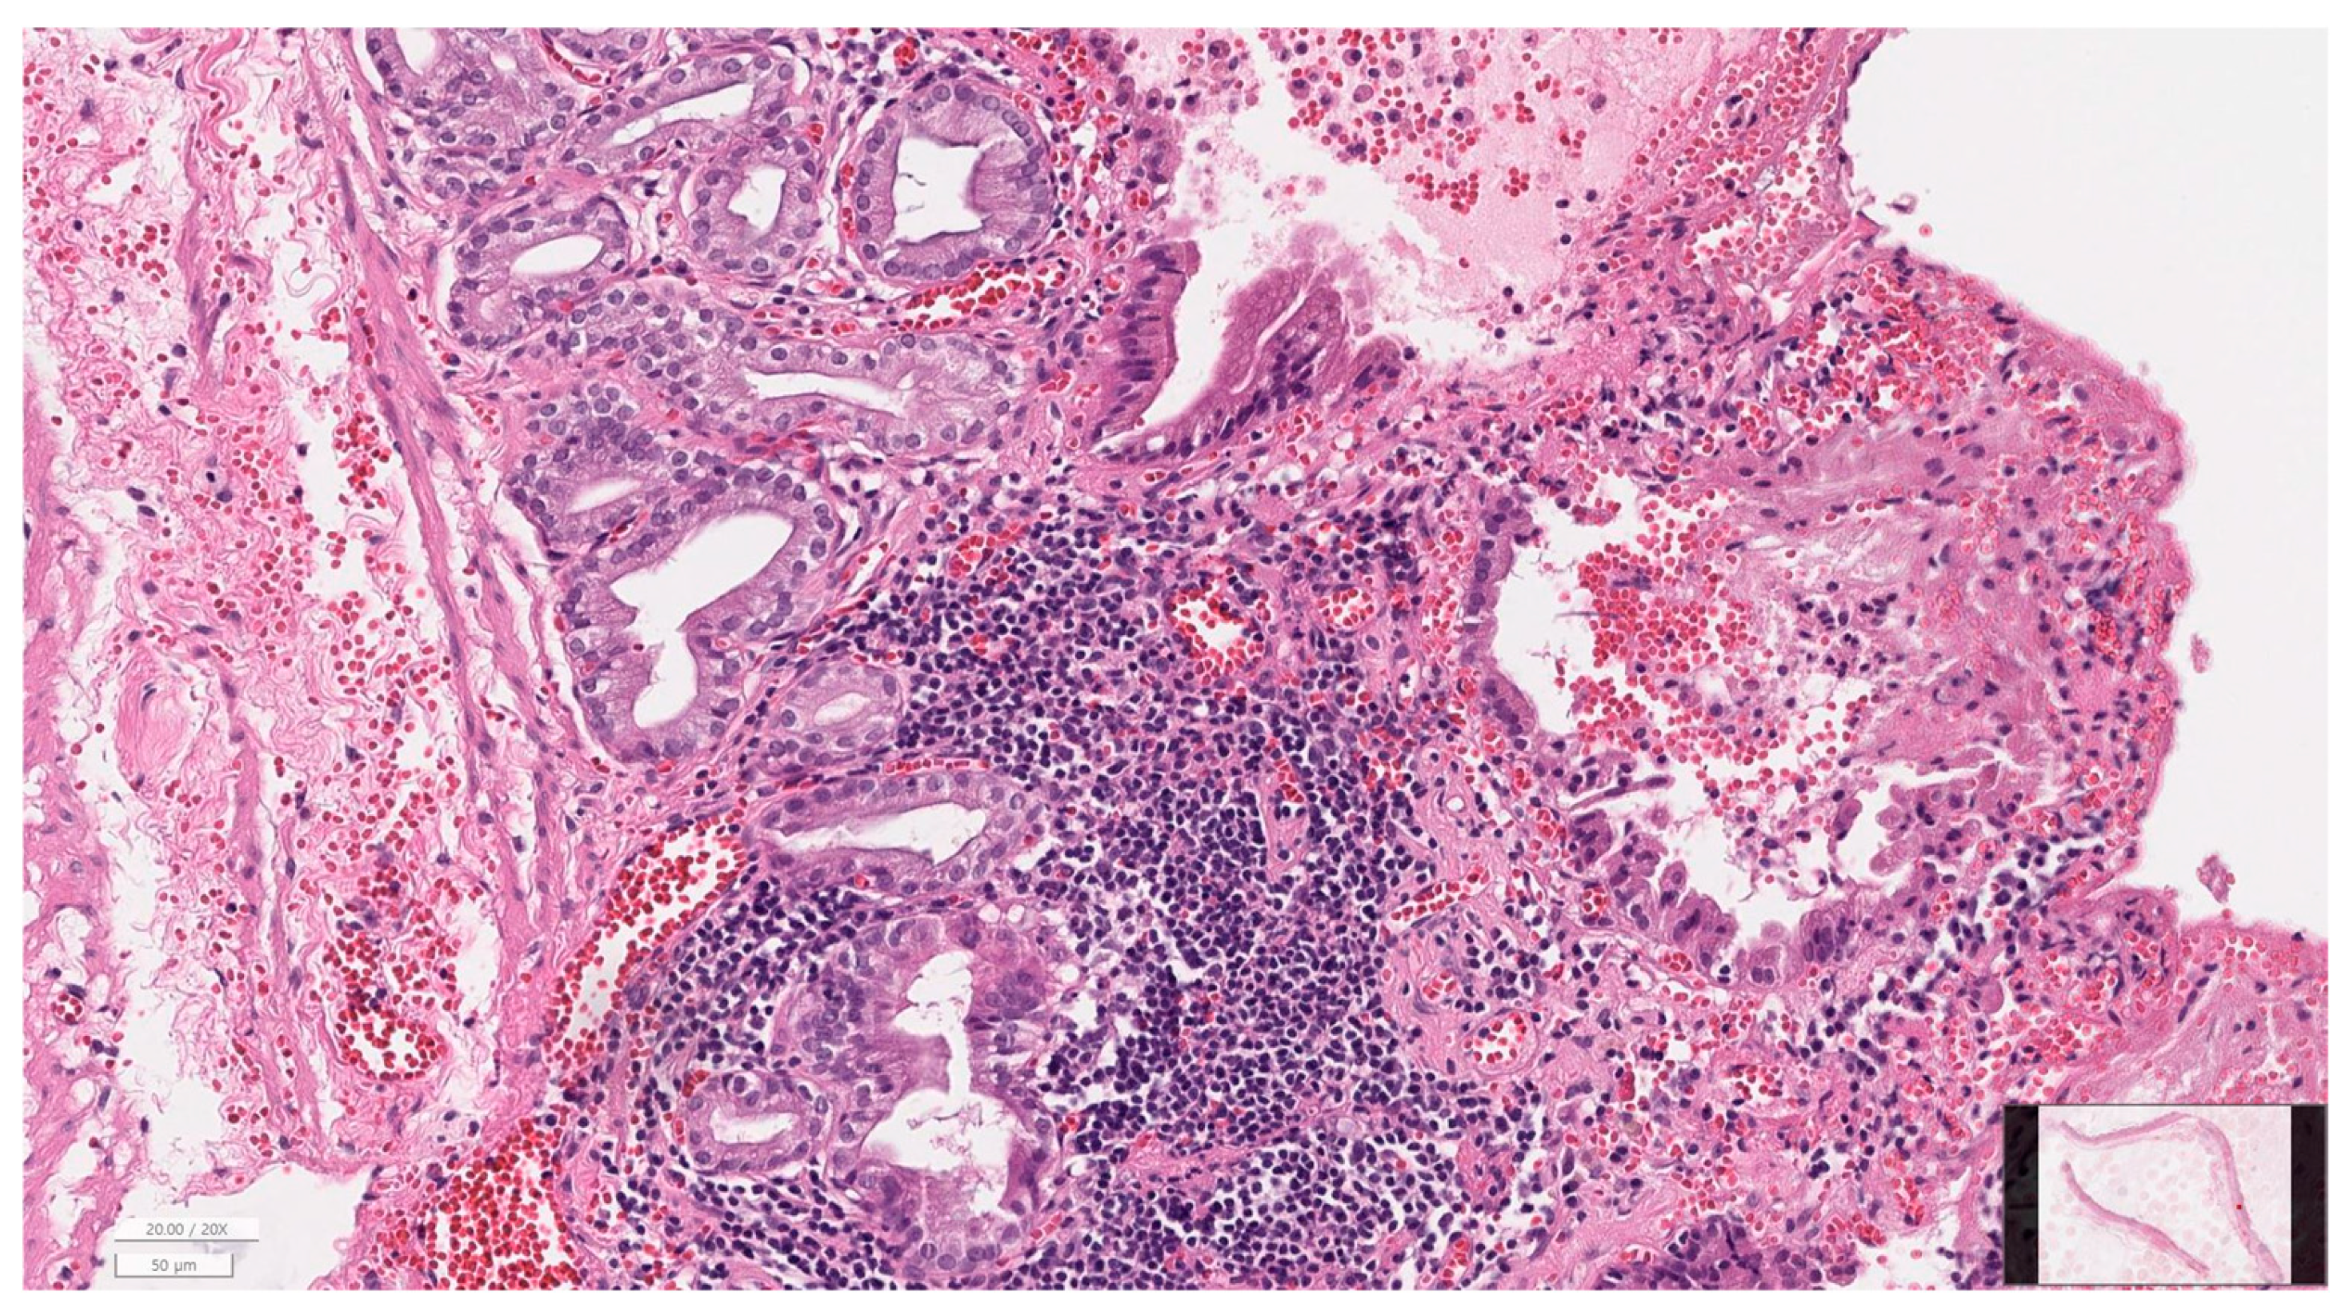

2.7. Histopathological Evaluation

3.6. Histopathology of Gallbladder and Liver